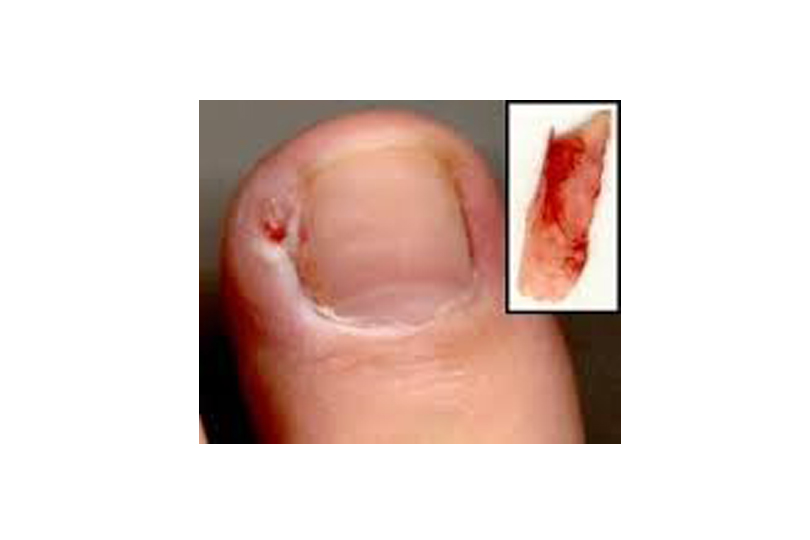

Ingrown Toe Nail Removal in London

Ingrown Toenail: What is it? An ingrown toenail occurs when the edge of the nail digs into the skin adjacent to it. This results into similar symptoms to a foreign body reaction; the skin becomes inflamed and swollen. The ingrown nail can also cause an infection, which results in much more inflammation and might spread […]

Ingrown Toe Nail Treatment Surgery

Ingrown Toe Nail People of all ages and from all walks of life suffer from ingrown toe nails. GP’s and A&E staff commonly prescribe antibiotics to help with the ensuing infection when the ingrown toe nail is not treated promptly with removing the ingrown nail spike. The minor surgical procedure is performed under local anaesthetic […]